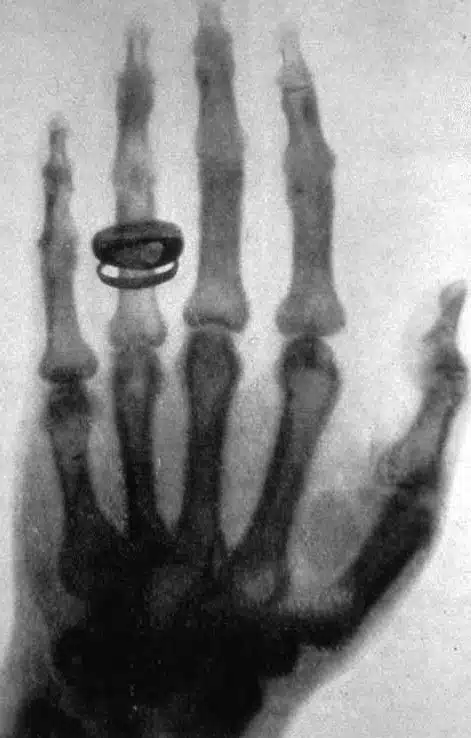

C’est en 1895 que Wilhelm Roentgen révèle le phénomène de rayonnement invisible lors d’une expérience réalisée avec son épouse.

Sa main est placée sur le parcours des rayons d’un tube cathodique. Au développement, il s’aperçoit que l’image représente l’ombre des os de la main d’une couleur sombre, et la chair de la main d’une couleur plus claire. La bague est également clairement visible.

Il en conclut que la chair est plus perméable aux rayons que les os ou la bague. Il appelle “X” ce rayonnement inconnu.

Les médecins comprennent immédiatement l’intérêt de cette découverte pour le secteur médical : c’est le début de la radiologie.